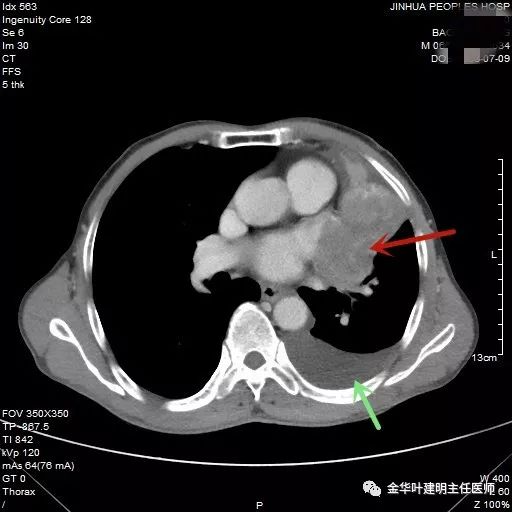

(病例资料2019年)金华的鲍某,今年66岁,前些天因胸闷不适到金华市人民医院就诊,住在内科病房,常规查胸部CT扫描发现左侧胸腔积液及左上叶不张。内科同事叫我去会诊,我看了CT片后认为:鲍某左上叶支气管堵塞伴有上叶不张,左侧还有中等量胸腔积液,首先考虑肺癌,以鳞癌可能性为大。是否能手术需要看相关检查有无远处转移,以及左侧的胸腔积液是不是恶性胸水。从临床经验来看,因为纵隔似乎无显著肿大的淋巴结,又存在上叶不张,胸水是肺不张导致的渗出性液可能性大些,恶性胸水的可能小些,当然这要经过相关的检查化验来确定。所以我建议先预约联系呼吸内科行纤维支气管镜检查以取得病理,确定是否确实是鳞癌(鳞癌才有手术机会,若小细胞癌到这样的程度,那就不能手术了),并予以胸腔穿刺置管引流胸水,并送病理科找癌细胞,送胸水常规、AFP与CEA、胸水生化、胸水细胞学、胸水培养等一系列检查,还抽取300毫升胸水送病理离心后沉渣行石蜡病理检查。结果胸水中未发现癌细胞,纤支镜病理是鳞癌,与之前判断一致,相应的胸部CT增强图像如下:

红色箭头示不张的肺,绿色示胸水

肿瘤与左肺动脉主干关系密切